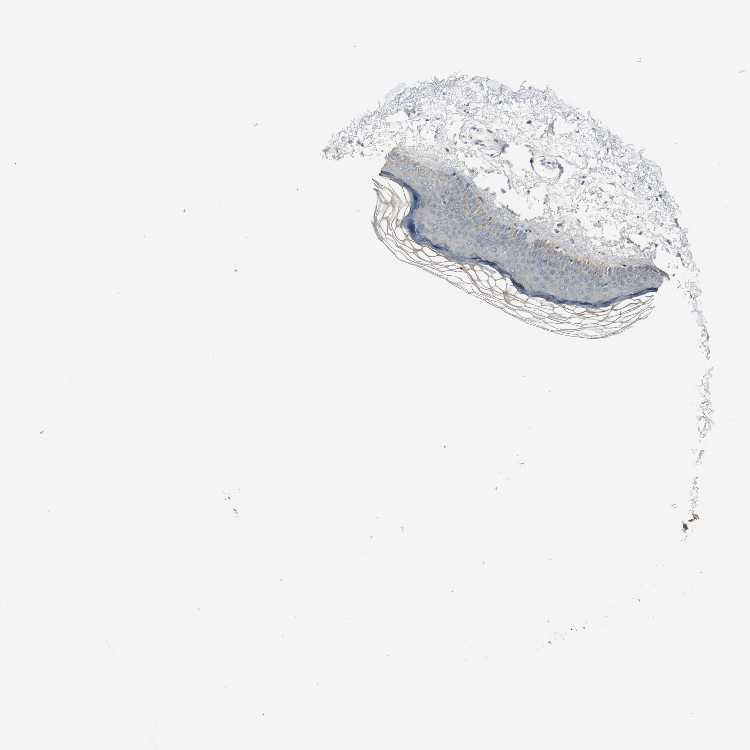

SKIN 1 - Antibody stainingi

Antibody staining in the annotated cell types in the current human tissue is reported as not detected, low, medium, or high, based on conventional immunohistochemistry profiling in selected tissues. This score is based on the combination of the staining intensity and fraction of stained cells.

Each image is clickable and will lead to virtual microscopy that enables deeper exploration of all samples and also displays staining intensity scores, fraction scores and subcellular localization as well as patient and tissue information for each sample.

Antibody HPA005899Antibody HPA005914

Langerhans Not detectedNot detected

Fibroblasts Not detectedNot detected

Keratinocytes LowNot detected

Melanocytes Not detectedNot detected